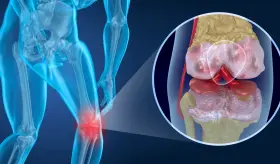

La gota es una enfermedad sistémica que puede afectar diferentes partes del cuerpo debido a la acumulación de urato monosódico en los tejidos.